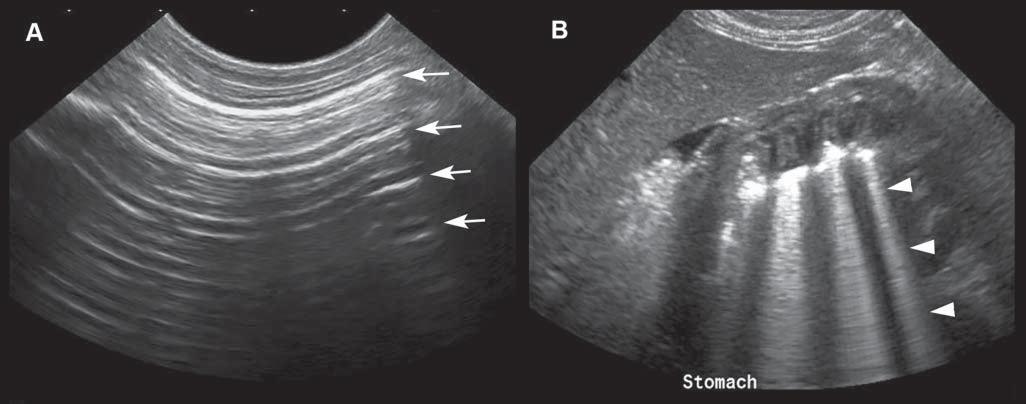

Shadowingisazoneofechoeswithreducedamplitude beyondahighlyattenuatingorreflectivestructure. Mostoftheincidentbeamisabsorbedand/orreflected attheinterface.Auniformlyanechoicshadowiscalled “clean,”whiletheterm“dirtyshadowing”isused whentheshadowisinhomogeneous(Rubin1991; Hindietal.2013).Cleanshadowingisencountered whenabsorptionoftheincidentbeamhappensata hyperattenuatinginterface,suchasbone,calculi,or compactforeignmaterial,thatislargerthantheultrasoundbeamwidth(Figure1.13A).Theshadowmaybe

Figure1.13. Acousticshadowingisapoorlyechoictoanechoiczonelocatedbelowahighlyattenuatinginterface.A: The cleanshadowbehindthislargegallbladdercholelithhasthetriangularshapeofthemicroconvexprobethatwasused. B: Dirty shadowingisnotedassociatedwiththemixedgasandstoolspresentinthecolon.Theextensiveartifactisshapedsimilarlyto thelongitudinalprobethatwasused.

Dirtyshadowing ispresentwhentheincidentbeam ismostlyreflected,suchasatasofttissue–gasinterface (Figure1.13B).